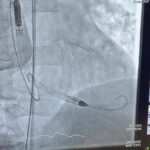

Il sistema IMPELLA è una sorta di pompa artificiale che ha lo scopo di adempiere alle funzioni del cuore nei momenti critici post infarto, mettendolo a riposo per il tempo necessario alla sua ripresa. Ciò consente non solo un recupero più rapido dei pazienti, ma anche di risolvere le situazioni di massima criticità e gravità. Il posizionamento di IMPELLA necessita dell’utilizzo di grossi accessi vascolari (introduttori di 14 FR in arteria femorale).

Da oltre tre anni, l’Emodinamica di Tivoli utilizza questo dispositivo sui pazienti critici e rappresenta uno dei pochi centri della Regione Lazio che utilizza il sistema IMPELLA senza il supporto di un reparto di chirurgia vascolare in sede. Tutto ciò è possibile grazie alle capacità e alle competenze di un team multidisciplinare, in grado di prevenire e gestire anche le complicanze, che ha sviluppato particolari abilità nella gestione interventista dell’apparato vascolare periferico.